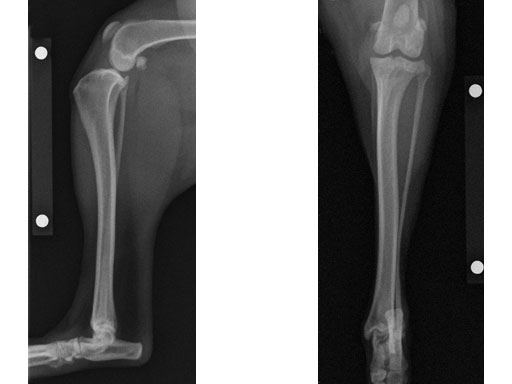

Case 3: Eight-year-old Australian cattle dog

(Case provided by Brian Beale, Houston, USA)

An 8-year-old, female, spayed, 24 kg Australian cattle dog. This breed has short stocky legs and is very energetic and strong. The added strength of the 3.5 mm plate over the TPLO 2.7 mm plate was an advantage. The smaller head profile and shorter length of the TPLO 3.5 mm small stature plate allowed it to fit nicely on this patient.